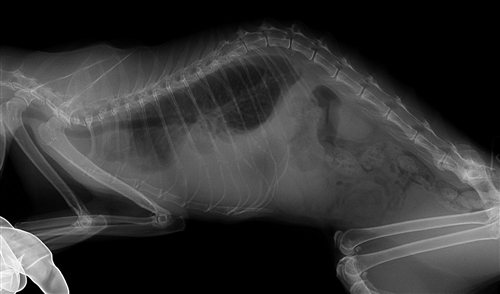

心筋症と思われる猫

5才の猫で2か月前からやせてきて2日前から食べない

とのことでした。

初診時は元気食欲廃絶、嘔吐、体温35.5 脈拍数100回

血液検査ではwbc22,900 Ht37.5% BUN62 クレアチニン2.9

レントゲンでは心臓自体の大きさは正常ですが心雑音が認め

られました。

エコー検査では左心室の壁の肥厚が認められました。

血流が悪くなってBUNが高くなったと思われました。

点滴、抗嘔吐薬、利尿剤、血管拡張薬、抗生剤、強心剤

で2日後に食欲が出てきました。

その後1年以上生きましたが肺水腫と胸水貯留を繰り返し

死亡しました。